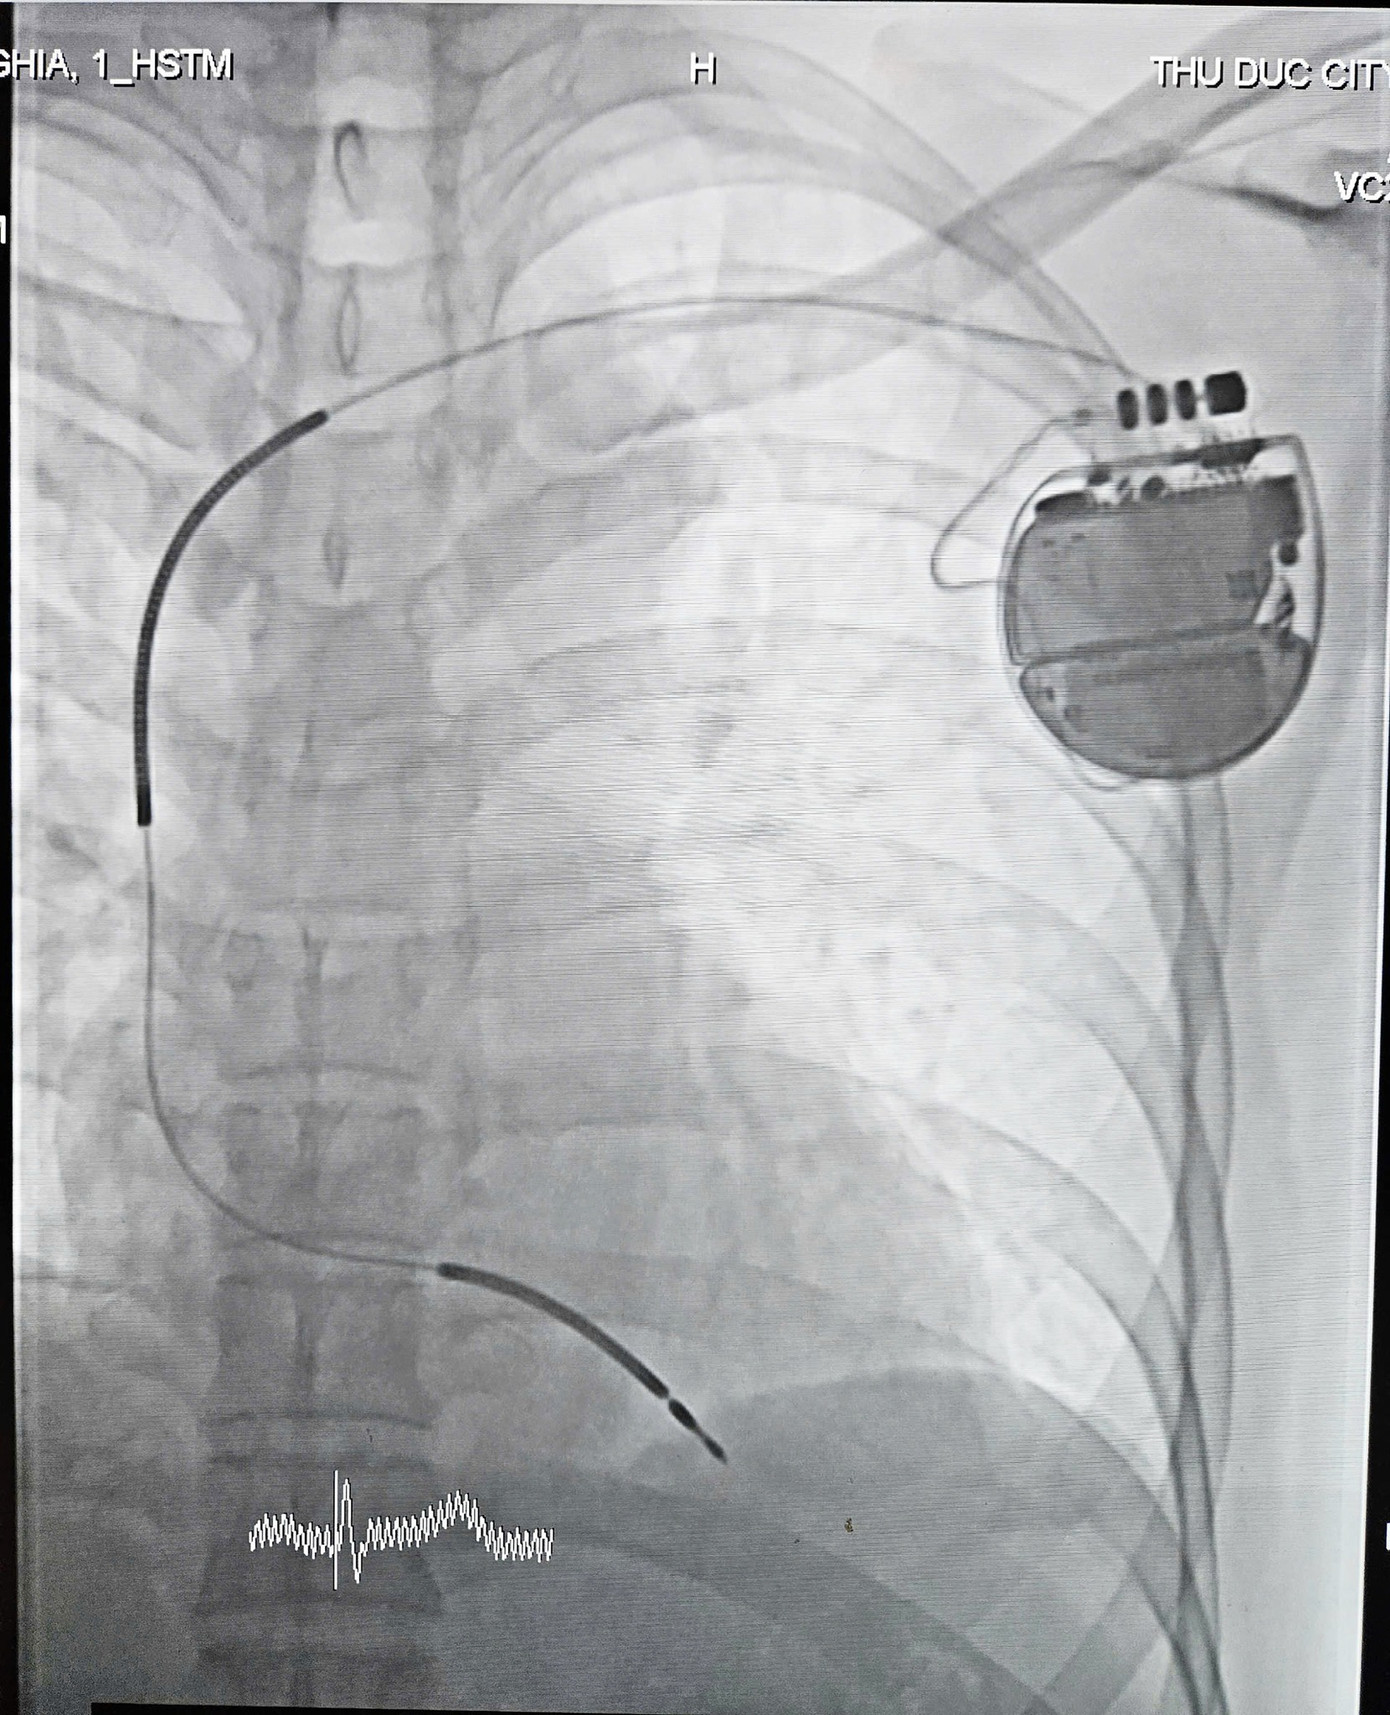

| Các bác sĩ tiến hành cấy máy phá rung tự động, ngăn chặn nguy cơ đột tử cho bệnh nhân |

Sau khi được cứu sống lần thứ hai, các bác sĩ đã tiến hành cấy ICD cho anh N. Ca phẫu thuật kéo dài 60 phút diễn ra thuận lợi: thiết bị được đặt dưới da vùng ngực, các điện cực nối trực tiếp vào buồng tim để giám sát và xử lý tình trạng rối loạn nhịp nguy hiểm. Sau đặt máy thành công, sức khỏe người bệnh đã ổn định, không ghi nhận nhịp nhanh thất hoặc rung thất tái phát.

| Thiết bị được đặt dưới da có khả năng kiểm soát nguy cơ rối loạn nhịp thất cho bệnh nhân |